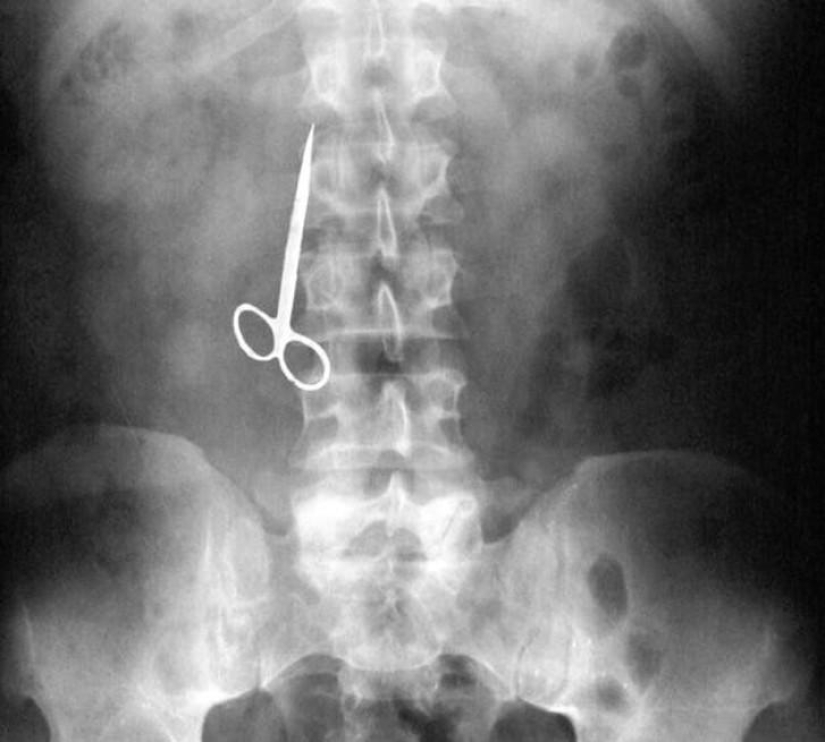

22. Surgical forceps.

24. Scissors.